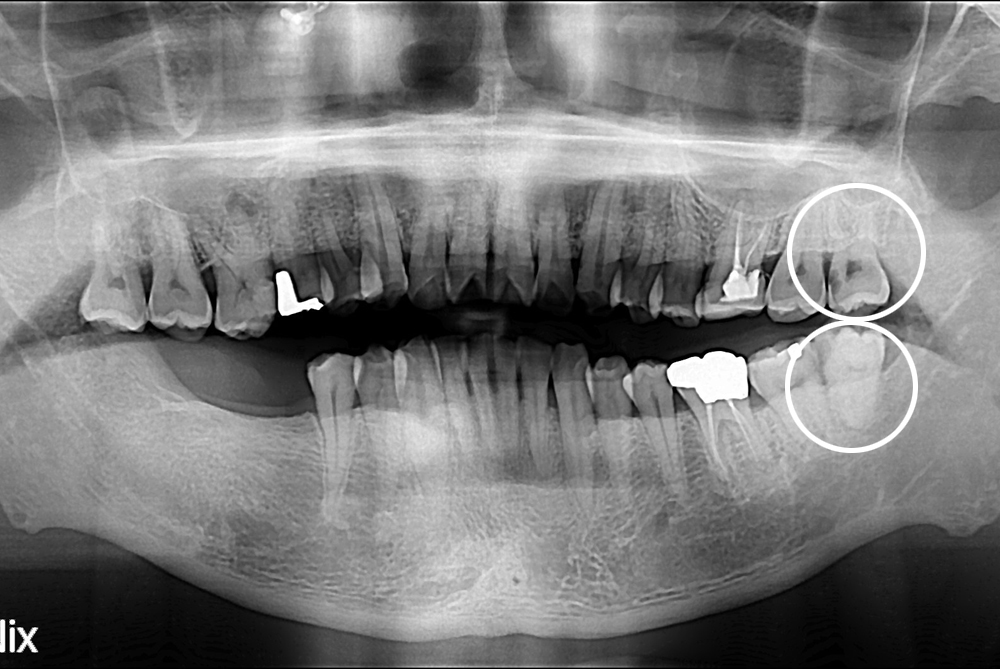

[사랑니] 난발치 사랑니 발치

치료전 : 2017-05-10